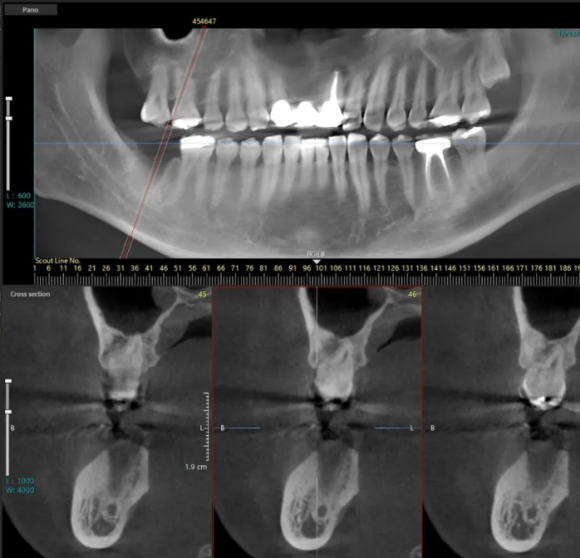

24.03.02 초진 파노라마

환자분께서는 오른쪽 아래 어금니가 붓고 통증이 심해 저희 병원에 방문 해 주셨습니다.

먼저, 엑스레이를 촬영해 치조골 상태를 확인해 보았는데요.

오래전 신경치료와 보철을 씌운 오른쪽 아래(사진상 왼쪽) 어금니 뿌리 주변으로 염증이 심해 치조골이 손상된 상태였습니다.

(빨간색 튜브처럼 표시한 곳이 하치조 신경관)

뿌리 주변으로 고름도 나오고 있고, 하치조 신경.관과 염증이 가까운 위치에 있어 주변 치아에 영향을 주기 전에 빠른 발치가 필요했는데요.